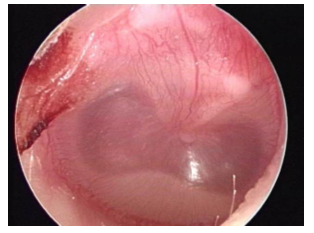

Retraction

When the TM gets pulled into the space behind it

When does retraction happen

Middle ear pressure is too low

Chronic negative pressure in middle ear leads to what

erosion of the ossicles